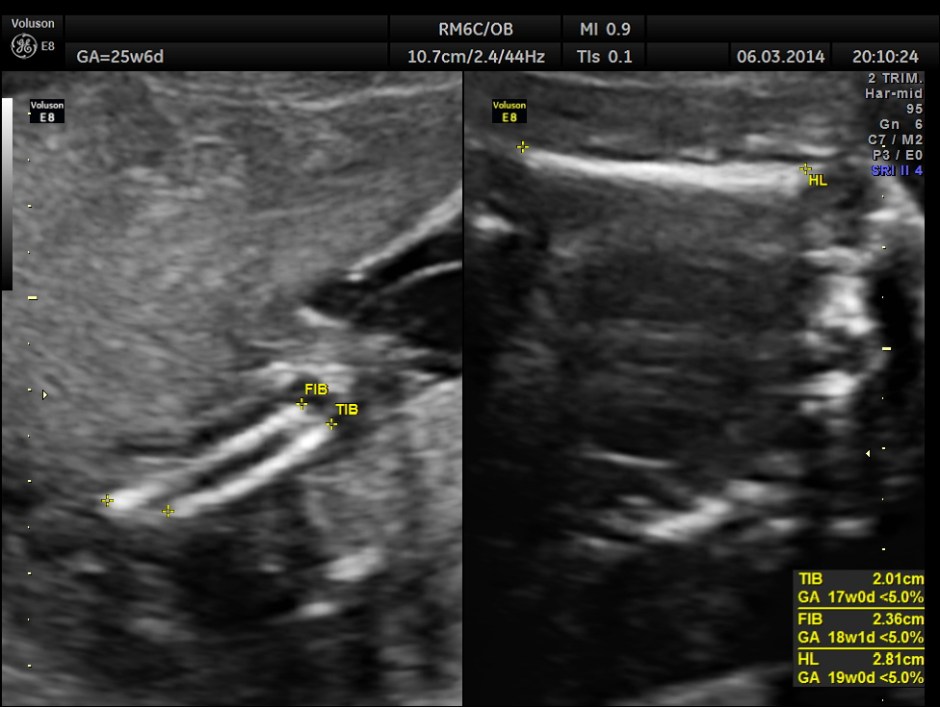

The GA was around 25 weeks , but the AUA was around 19 to 20 weeks. All parameters – BPD, HC, AC, FL are < 2.3 %tile and all other long bones are < 5.0 %tile.